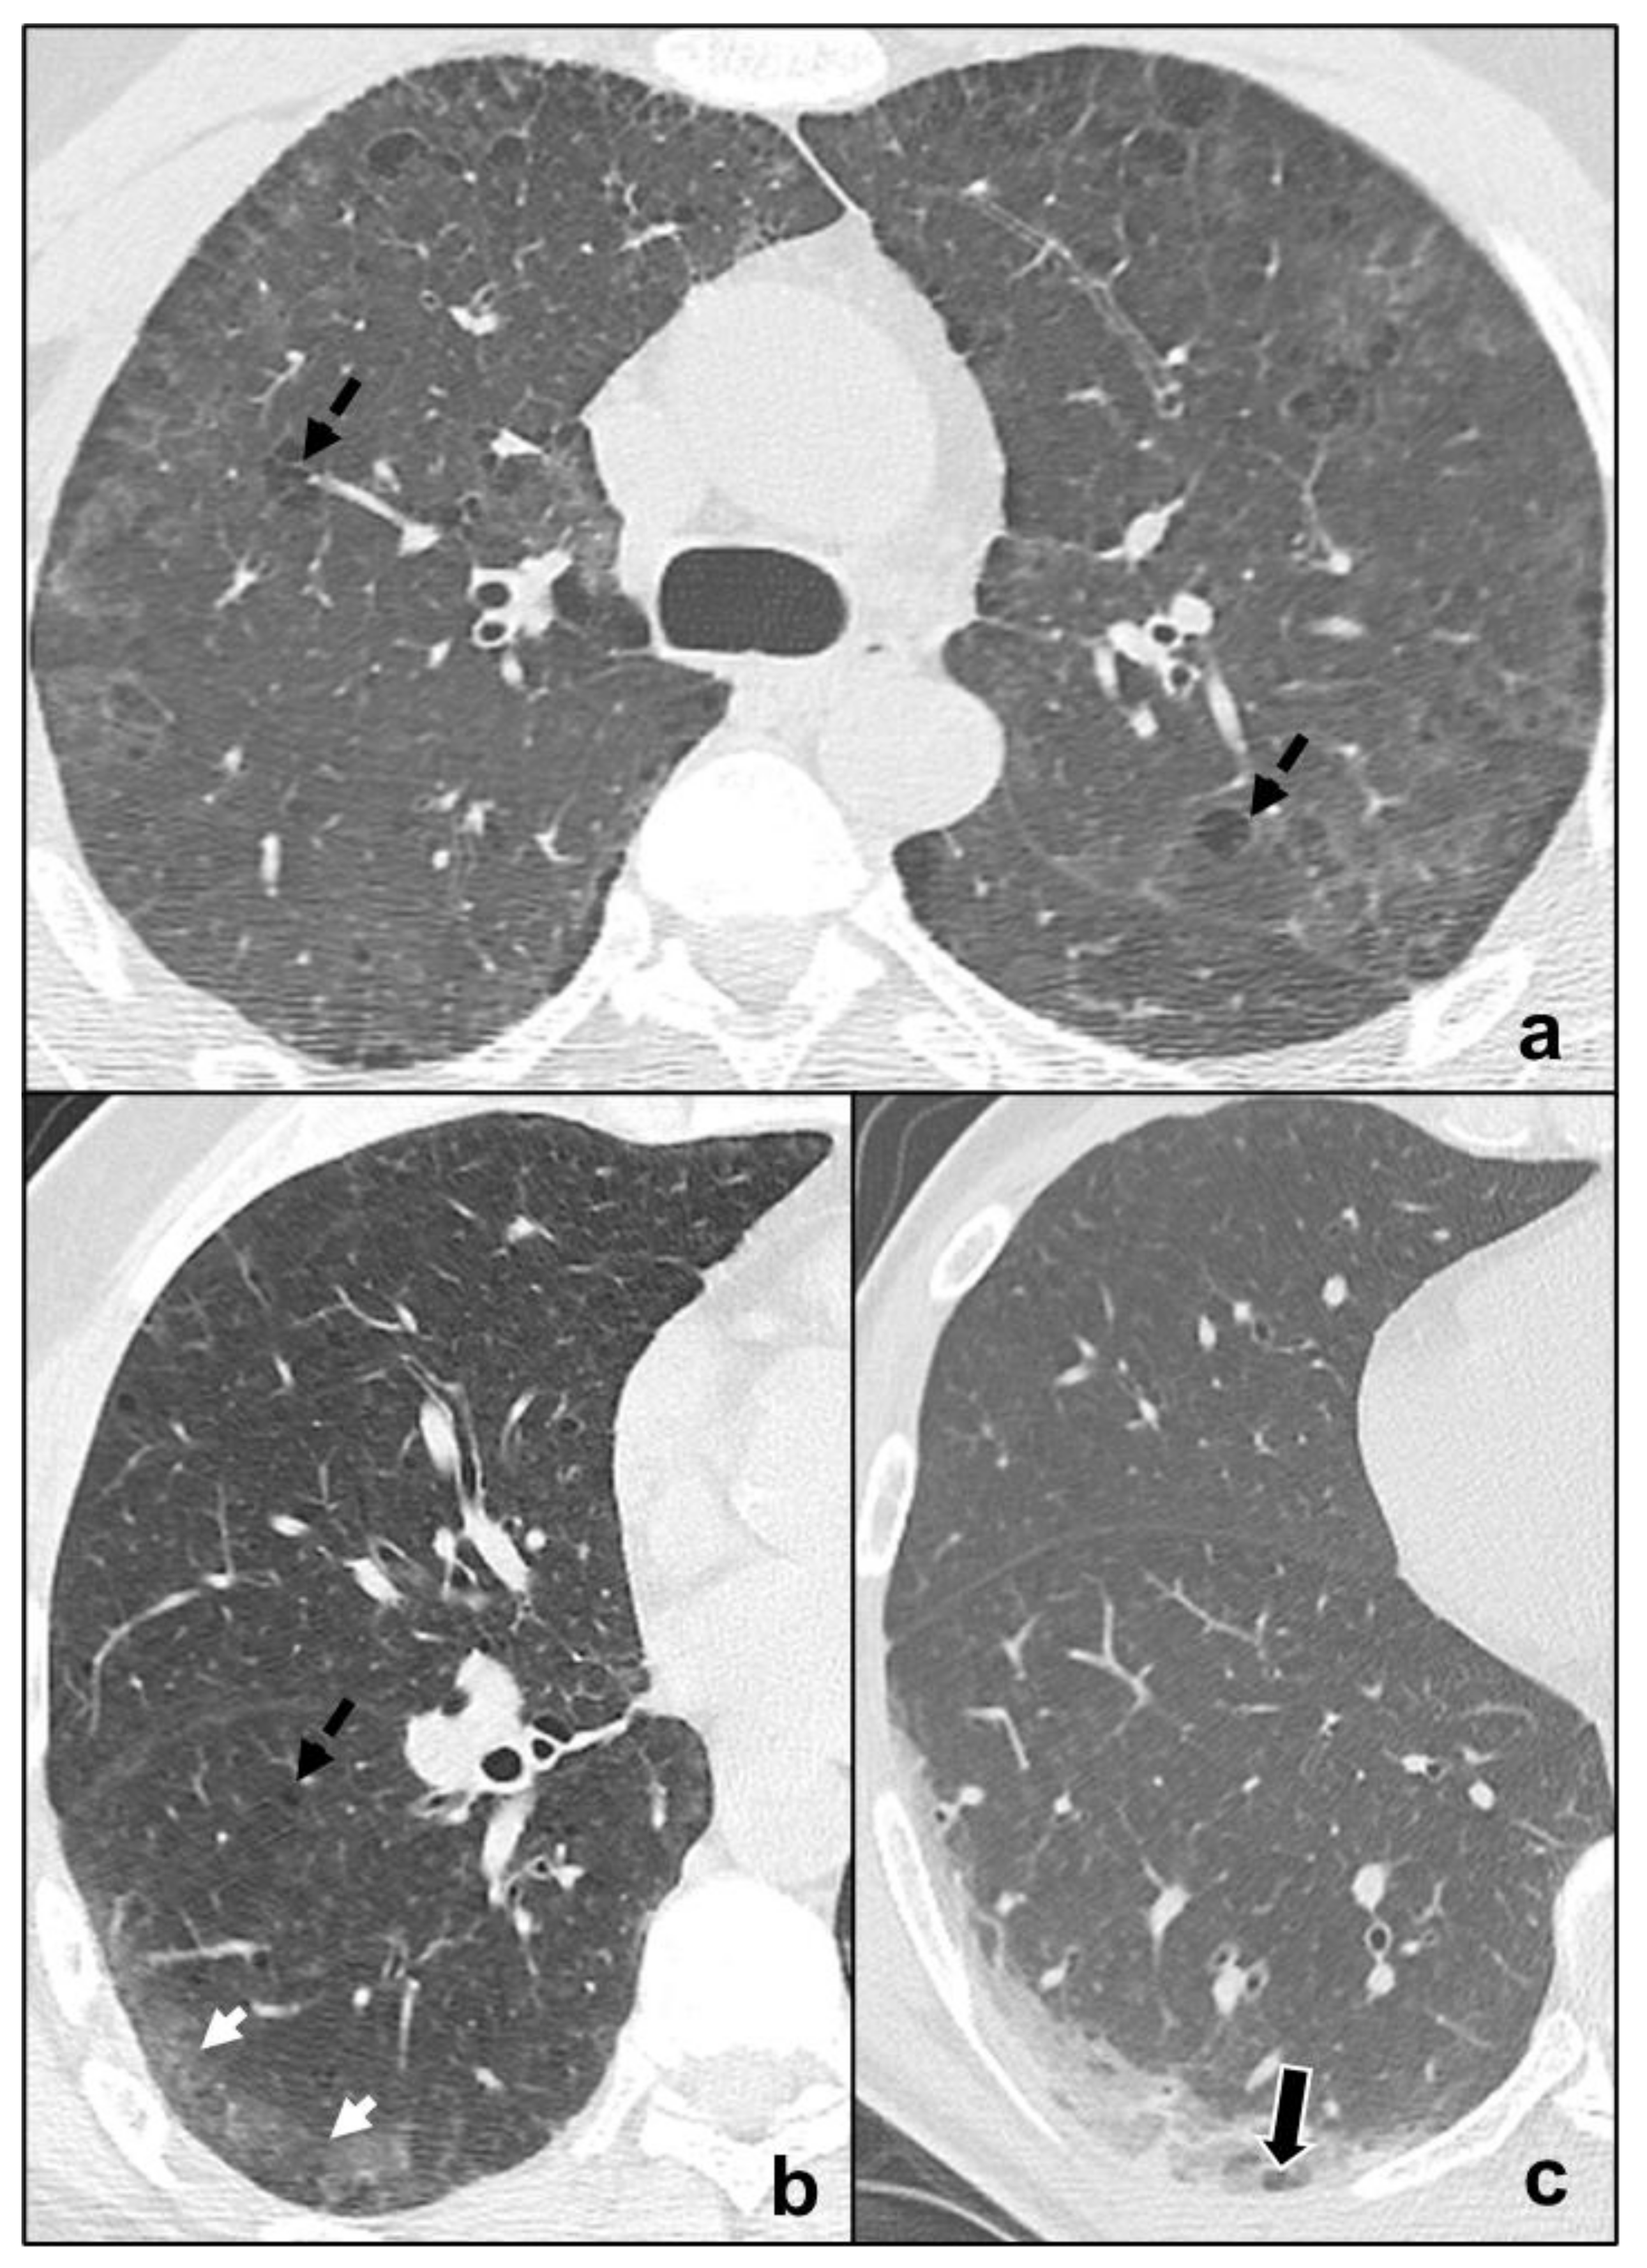

Figure 4.

Major IIPs: Smoking-Related IIPs. In (a), RB-ILD is characterized by bilateral widespread ground glass opacities, centrilobular nodules, and centrilobular (black dotted arrows), and subpleural emphysema; in (b,c), DIP shows subpleural ground-glass areas (white arrow in (b)) associated with reticular, thin opacities and centrilobular (black dotted arrows) emphysema, while in (c), perivascular cysts are evident (white-bordered black arrow in (c)).

Desquamative Interstitial Pneumonia

It is an IIP predominantly affecting smokers, but also documented in non-smokers and presenting with cough and dyspnea [19]. It is characterized by peripheral, basal ground glass opacities. Coexistence of linear or reticular opacities and perivascular cysts indicates fibrotic changes [5,40] (Figure 4b,c). Despite radiological differences with RB-ILD, differential diagnosis may be difficult with possible overlapping between the two pathologies.

It is smoking-related IIP presenting with mild dyspnea and cough, diffusively affecting lungs or with upper pulmonary lobe predominance. Chest CT is characterized by centrilobular nodules, bronchial wall thickening, and ground glass opacities [38,39]. Frequently, coexisting centrilobular emphysema is described in relation to smoking habits [5] (Figure 4a).